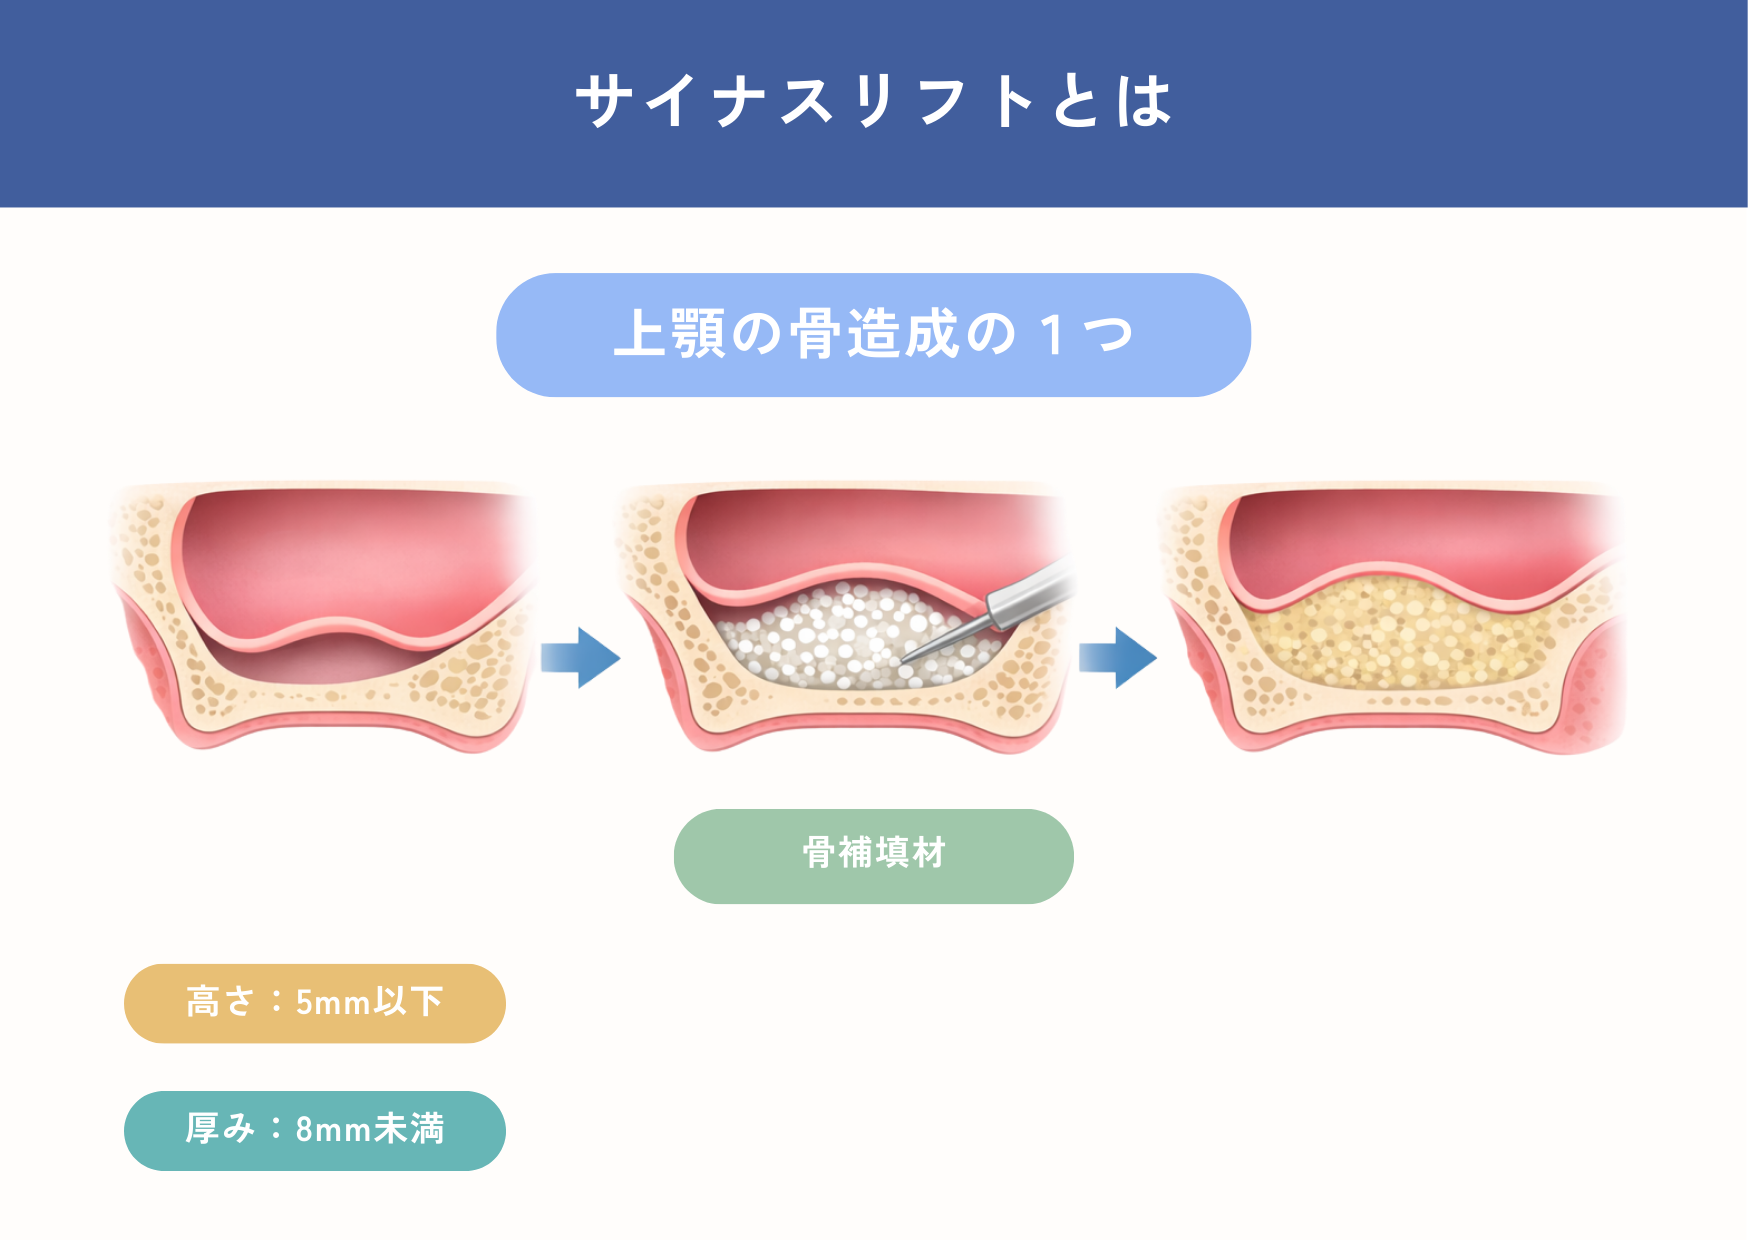

「骨が3mmしかない」といった重度の骨不足の方に選ばれるのがサイナスリフトという術式です。他院で断られた方の多くは、この術式が必要なケースです。

3-1 サイナスリフトの仕組み

サイナスリフトは歯茎の横側からアプローチし、上顎洞の粘膜を直接目で確認しながら、専用の器具を用いて慎重に持ち上げていく方法です。粘膜を破らないように細心の注意を払いながら操作し、持ち上げたスペースに骨補填材を入れることで、インプラントを支えるための骨を作ります。ソケットリフトと比べてより広い範囲のスペースを確保できるため、骨の不足が大きい場合でも対応でき、1度の処置で十分な骨の量を作ることが可能です。上顎の骨が大きく失われている方にとって、安全性と確実性を重視した方法といえます。

3-2 誰に向いている?

・骨の厚みが3mm〜5mm程度と、極めて薄い方。

インプラントを支えるための骨がほとんど残っておらず、ソケットリフトなどの比較的軽い方法では十分な骨量を確保できないケースに適しています。

・広範囲にわたって複数のインプラントを検討している方

奥歯を複数本失っている場合やブリッジ・入れ歯に代わる安定した治療を希望される方では、広い範囲で骨を作れるサイナスリフトが有効です。

・他院で「骨が足りないため難しい」と診断された方